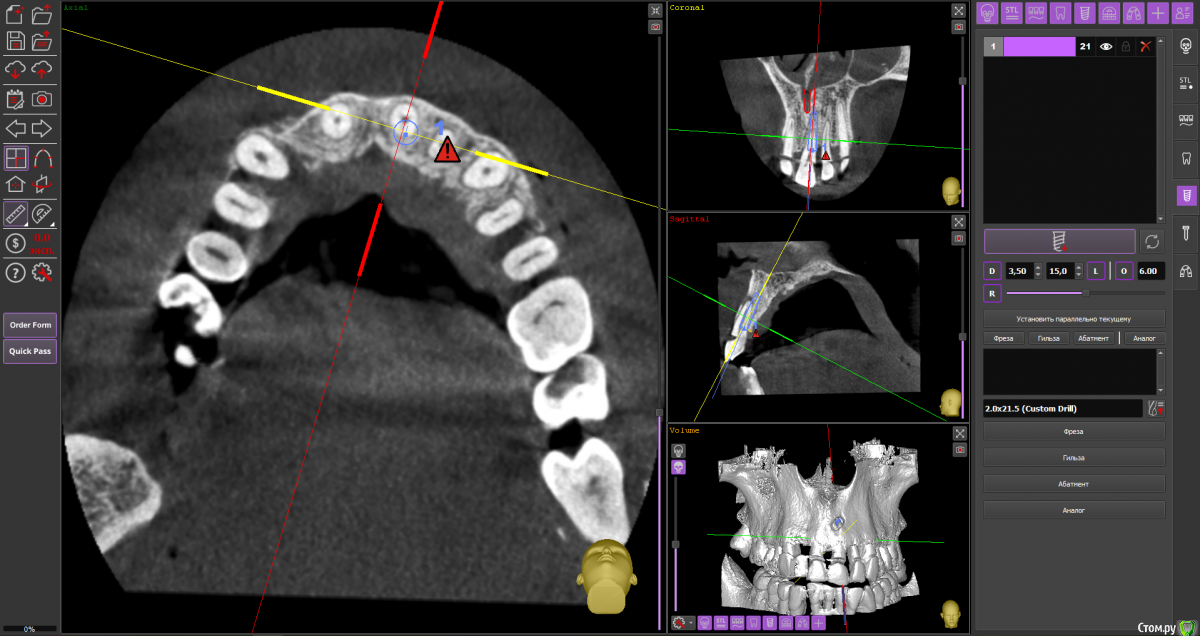

almaz7888 Опубликовано 28 января, 2021 Поделиться Опубликовано 28 января, 2021 Доброе утро коллеги! Планирую одномоментную имплантацию в область 2.1 зуба ( AnyRidge 3.5*11.5). В области апекса костный дефект. Думаю заполнить ксенографтом и перекрыть резорбируемой мембраной 1.5*2.0. Думал насчет спейсера Стоит ли такой имплант сразу нагрузить? или же лучше сделать адгезивный мост. Ссылка на комментарий

alboard Опубликовано 28 января, 2021 Поделиться Опубликовано 28 января, 2021 В том положении, которое на кт, сомневаюсь, что получите торк и сможете нагрузить... Взять подлиннее, поставить небнее и заглубить еще 4 Ссылка на комментарий

Irouil Опубликовано 28 января, 2021 Поделиться Опубликовано 28 января, 2021 Винт длиннее, выход в резцовый, стт, временная коронка 1 Ссылка на комментарий

almaz7888 Опубликовано 28 января, 2021 Автор Поделиться Опубликовано 28 января, 2021 Спасибо, тогда возьму 3.5*15. А резцовый нерв коагулирую и заполняю канал графтом или же можно без прижигания обойтись? Ссылка на комментарий